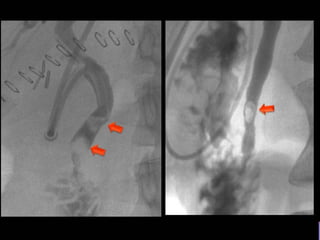

COLEDOCOLITIASIS

RESIDUAL

• #15 Colangiografia postqx: AP oblicua muestra varias imágenes radiolucidas en via biliar a nivel de colédoco(flechas)

• #19 Imagen por fluoroscopia evidencia imágenes radiopacas de bodes definidos en via biliar a nivel de colédoco A RELACIONAR CON COLEDOCOLITIASISS RESIDUAL